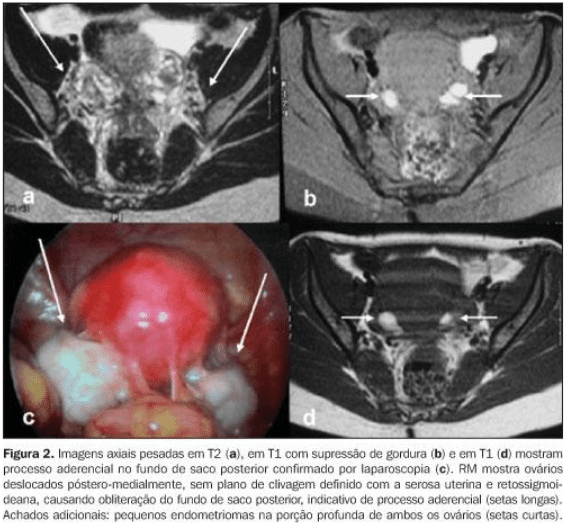

Abaixo vemos 2 ressonâncias magnéticas pélvicas em T2. Na primeira, percebe-se um tecido endometriótico extenso em região posterior ao colo uterino. Na segunda imagem, em uma sequencia sagital, tem-se um tecido endometriótico retrouterino com comprometimento da parede intestinal.

A supressão de gordura é útil porque muitas vezes as lesões de endometriose têm um sinal semelhante ao da gordura. Ela pode melhorar a visibilidade das lesões. Na imagem B da figura abaixo, é possível ver isso.